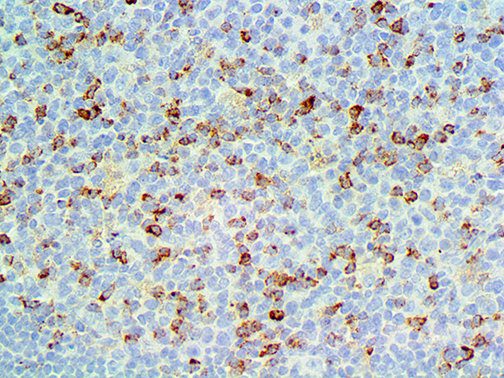

It is the ICU physician who is most likely to witness one of the deadliest manifestations of the abnormal immunological response, the cytokine storm syndrome (CSS). This response is also referred to by some as the cytokine release syndrome (CRS). CSS is characterized by continuous activation and expansion of macrophage and lymphocyte populations, which secrete large amounts of cytokines, causing the cytokine storm. This massive cytokine release is akin to hemophagocytic lymphohistiocytosis (HLH) disease, a syndrome characterized by initial unchecked and persistent activation of cytotoxic T lymphocytes and NK cells.

Clinical and laboratory manifestations of HLH include fever, enlarged liver and/or spleen, neurologic dysfunction, coagulopathy, liver dysfunction, cytopenias (i.e., low levels of erythrocytes, leukocytes, and/or platelets), hypertriglyceridemia, hyperferritinemia, hemophagocytosis, and eventually diminished NK cell activity as the immune system becomes progressively paralyzed. HLH can be familial (primary HLH) or secondary to another disease process (sHLH), such as rheumatic disease, in which it is referred to as macrophage activation syndrome (MAS, characterized by elevated ferritin).